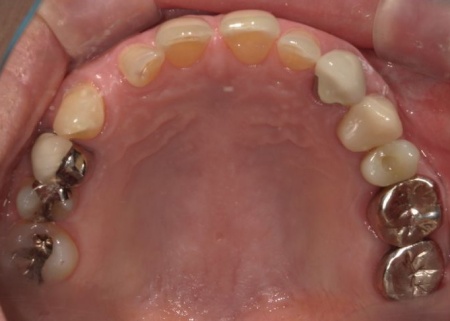

70代女性 歯根が割れた左下奥歯を抜きインプラントで噛み合わせを回復させた症例

後日、インプラントと骨がしっかりと結合したら、精密な型取りを行い、被せ物を作製します。

最後に完成した被せ物を装着し、痛みや違和感がないか、見た目や噛み合わせに問題がないかを確認して、治療を終了しました。